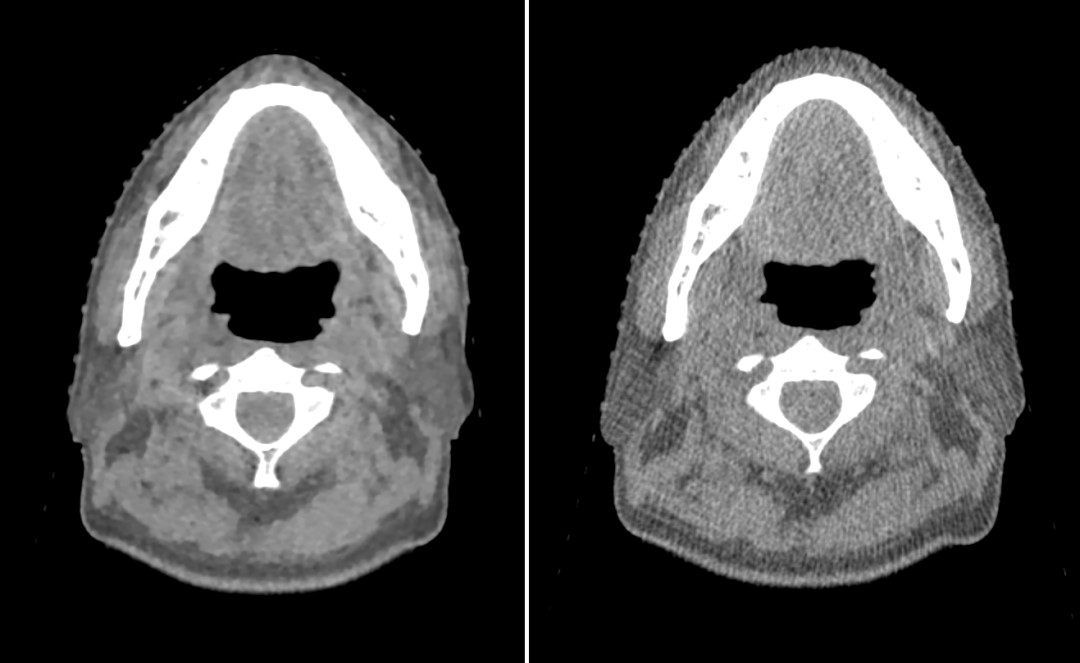

图3为本科室一头颈部病例在Head模式下iCBCT图像和标准模式kV CBCT图像的对比图,图4为使用成年男性CRIS模体Pelvis扫描模式下iCBCT图像和标准模式kV CBCT图像的对比图。自全新一代Halcyon加速器在本科室应用以来,其iCBCT技术带来的图像质量的提高,得到了医生、物理师和放射治疗师的认同。

(左图)iCBCT图像 / (右图)标准模式CBCT图像

图3 一头颈部肿瘤病例Head扫描模式下CBCT图像对比